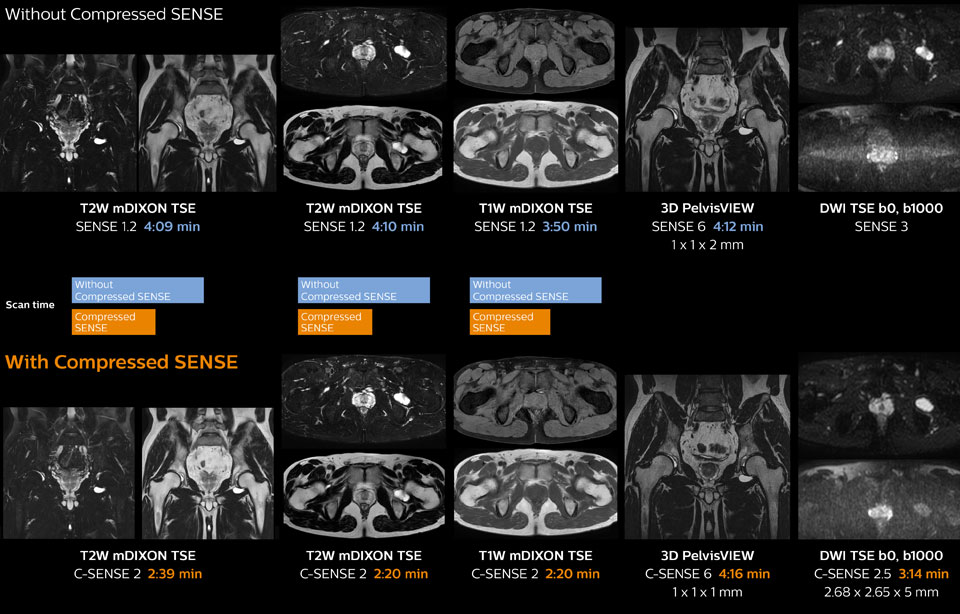

Hip with synovial cyst w/wo Compressed SENSE

Ingenia 1.5T MRI scans with and without Compressed SENSE are compared for this case of a hip with a synovial cyst. In the mDIXON sequence, the Compressed SENSE factor used is higher than the SENSE factor on the previous scan, so scan times are reduced without sacrificing image quality. The high resolution images are useful for diagnosing of a detailed dissection. The diffusion TSE with Compressed SENSE shows reduced noise compared to the Diffusion TSE with SENSE and the artifact has disappeared.

So in this case, Compressed SENSE helped in reducing scan times of the examination. The Compressed SENSE images allowed the radiologist to confidently diagnose the lesion and see the anatomic relationships of the abnormal signal to the surrounding structures.

Pelvis with myoma – comparison w/wo Compressed SENSE

In this MRI exam of pelvis in a patient with myoma, Compressed SENSE is used to accelerate individual sequences and thus the entire examination on Ingenia 1.5T. Compressed SENSE allowed for a decrease in scan time for the T2 TSE from 3:38 to 1:46 minutes. The Compressed SENSE images in this case show fewer motion artifacts than the images from the previous protocol with SENSE. In 3D PelvisVIEW, the Compressed SENSE images have a higher and isotropic spatial resolution with a scan time similar to the SENSE sequence. The improved spatial resolution and better contrast in the myometrium of the uterus allowed radiologist Dr. Koyama to confidently diagnose the cancerous lesion in the uterus. The use of Compressed SENSE accelerates scanning times and increases spatial resolution in 3D PelvisVIEW.